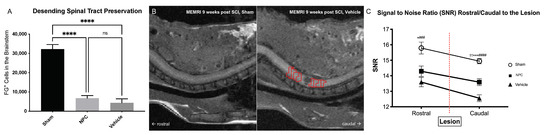

2.3. Preservation or Regeneration of Descending and Ascending Spinal Tracts

4.5. Retrograde Fiber Labeling and Manganese-Enhanced MR-Imaging